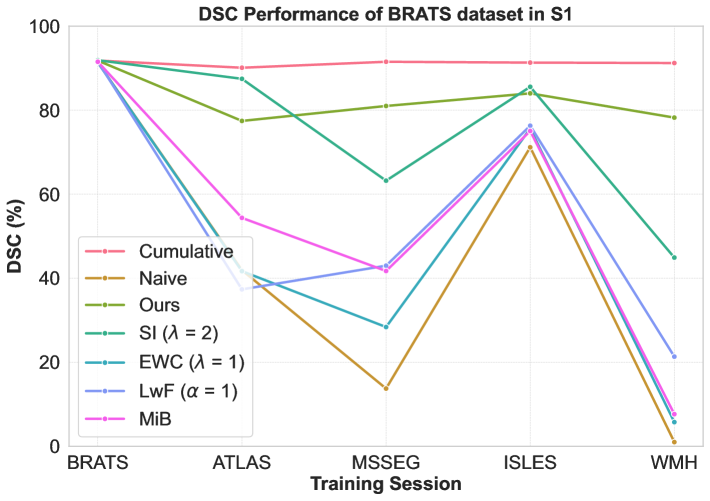

Performance comparison with others: For the considered medical applications, the primary concern will not be on improving zero-shot performance (FWT) but rather on minimizing forgetting (BWT) and enhancing the average DSC of the model (ACC and ILM). While FWT is reported for completeness, our analysis emphasize ACC, ILM, and BWT. Table 2 presents the ACC, ILM, BWT, and FWT values for all methods across sequences S1, S2, S3, and S4. Across all sequences, CL approaches (GDumb, Replay, MiB, LwF, SI, EWC, and the proposed method) mostly outperform naive training, highlighting the importance of mechanisms to mitigate catastrophic forgetting in UNet-based segmentation tasks. Further, as expected, approaches storing past data partially (Replay, GDumb) or fully (cumulative, joint training) show higher performance compared to methods (naive, MiB, LwF, SI, EWC, and the proposed approach) with no access to past exemplars. When comparing the proposed method to other buffer-free approaches (MiB, LwF, SI, EWC), it consistently achieves superior performance in all the sequences S1, S2, S3, and S4. Unlike these existing CL methods, which penalize large deviations from previously learned weights through response-level regularization terms in the training loss, the proposed approach introduces a drift-based dynamic penalization factor along with a latent-level regularization. This drift-based dual distillation allows for more effective mitigation of catastrophic forgetting. The proposed method shows a positive gain in (ACC, ILM, BWT) over best performance achieved among state-of-the art buffer-free approaches (blue colored in Table 2). Specifically, we observe an improvements of (25.51%, 9.23%, 34.34%) in S1, (6.57%, 25.28%, 31.85%) in S2, (4.85%, 11.02%, 40.15%) in S3, and (7.67%, 10.65%, 17.62%) in S4. For intuitive visualization, radar plots for S1, S2, S3, and S4, comparing cumulative, naive, the best-performing buffer-free methods, and the proposed approach are provided in Fig. 6 of Appendix.

Performance of a dataset in different sessions: We closely analyze CL model’s performances on first/second dataset upon learning other datasets in a given sequence. Specifically, Figure 3 shows DSC for BRATS in S1 and S2, ISLES in S3, and WMH in S4, with cumulative training included for reference. While cumulative training offers stable results, it requires access to all previous datasets, which is impractical in real-world scenarios. The naive approach shows significant DSC degradation, with high standard deviations of 33.91 (S1) and 40.23 (S2), 26.31 (S3), and 24.78 (S4) reflecting instability. In contrast, our CL strategy maintains stability, with much lower standard deviations of 5.19 (S1), 14.51 (S2), 11.37 (S3), and 15.50 (S4) highlighting its increased robustness against forgetting. Other buffer-free CL methods (MiB, SI, EWC, LwF) show better performance than naive training (Table 2) but still exhibit instability in DSC, with standard deviations of (28.80, 17.86, 31.14, 25.98) for S1, (36.75, 36.75, 35.85, 40.10) for S2, (25.43, 23.51, 25.65, 25.11) for S3, and (25.06, 15.51, 22.84, 23.55) for S4. While these methods perform well for natural images, their effectiveness is limited in brain MRI segmentation under domain shifts. In contrast, our approach delivers better stability and mitigates catastrophic forgetting effectively. Detailed segmentation visualizations for BRATS are provided in Appendix A.

Impact of dataset orders: We study the impact of different sequences on overall performance. We analyze ACC, ILM, BWT by best performing other CL methods and proposed approach for S1-S4 in Table 2 (summarized in Table 4, Appendix). We can see that best ACC is poor in S2 (28.54) and S3 (35.85) as compared to that in S1 (54.31) and S4 (50.67). Notably, all methods (except EWC) showed performance degradation when ATLAS (a single-modality dataset) was introduced later in sequences (S2, S3), adversely impacting the generalization of previously acquired knowledge in the model. This occurs because “modality dropping”, a critical generalization technique, cannot be applied to ATLAS due to its single-modality nature. Consequently, learning ATLAS in the later stages negatively impacts the model’s prior generalization capability. In contrast, when we learn datasets with fewer modalities at the start of sequences (S1 and S4), their negative effect is covered at later stages when we learn datasets with more modalities.